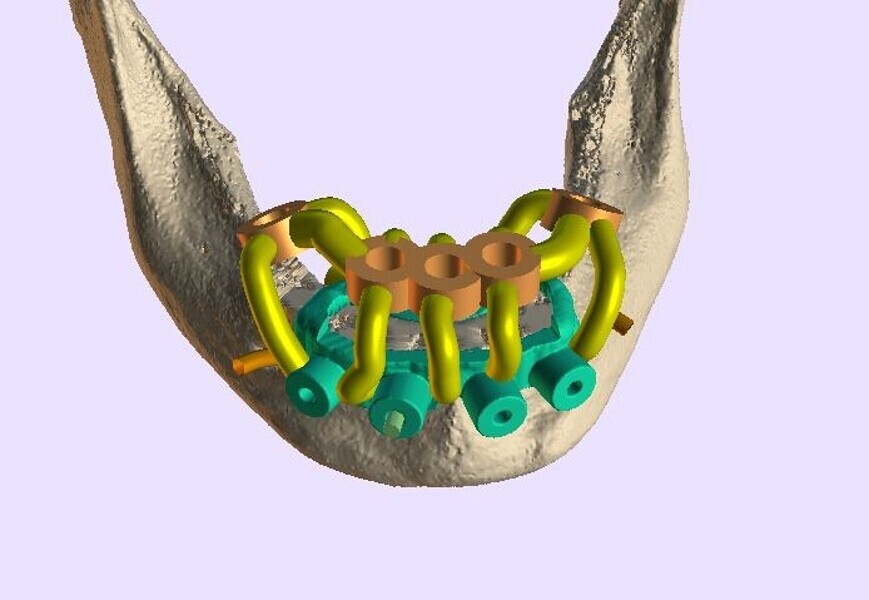

The preliminary plan consisted of placing implants in strategic positions to support implant-supported fixed restorations accurately delivered with the implementation of static, sequential surgical guides (Fig. 3).

Fig. 3a: Six implants planned for maxillary arch fixed restoration.

Fig. 3b: Five simulated implants with two tilted to avoid the inferior alveolar nerves in the mandibular arch.